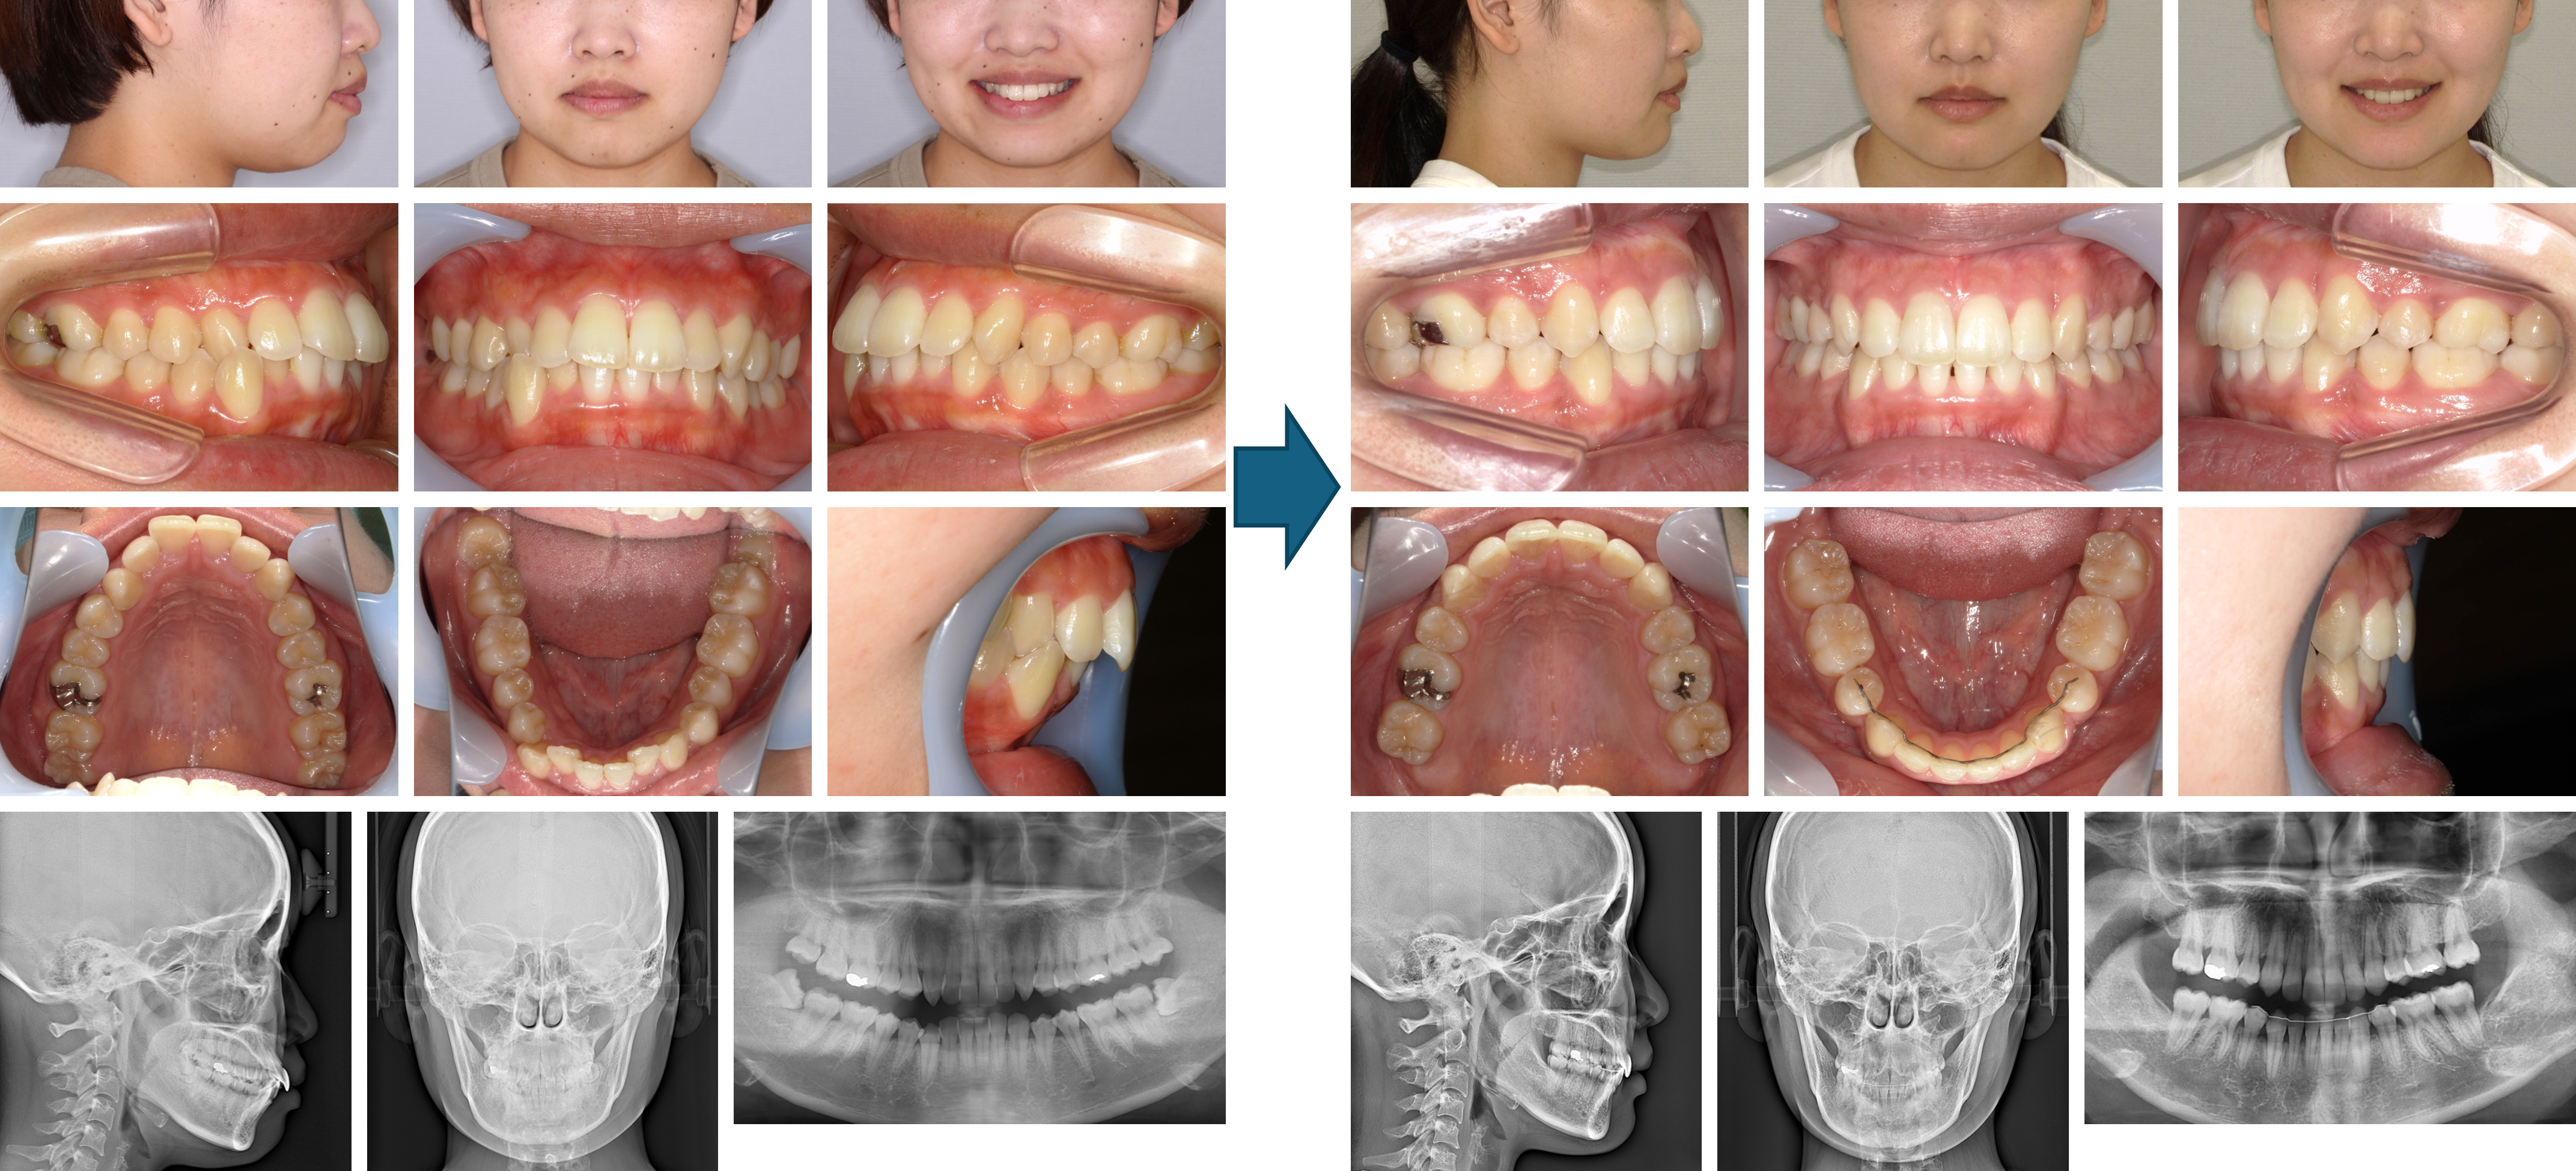

【治療例】初診時年齢:24歳2か月 / 性別:女性 / 主訴:上の歯2本が内側にはえていることと右上の八重歯が気になる

症例の概要:上下とも歯が大きくさらに下顎歯列に対して上顎歯列が狭かったため、上顎はクワドヘリックス装置で歯列の拡大を行った後、上下とも歯を抜歯する治療法を選択した。下顎骨の後退位と右方偏位が認められたが、トランスパラタルアーチとハイプルヘッドギアをしてくれたおかげで、治療後は顔貌の改善と緊密な咬合を獲得することができた。

主訴:口元の突出感と上の歯2本が内側にはえていることと右上の八重歯が気になる

診断名:下顎骨が後退位と右方偏位した骨格性Ⅱ級、ハイアングルの上顎前突症例

使用した主な装置:マルチブラケット装置、クワドヘリックス、ハイプルヘッドギア、トランスパラタルアーチ、顎間ゴム

抜歯/非抜歯および抜歯部位:抜歯(上下顎両側第一小臼歯)

治療期間:2年4か月

治療回数:25回

リスクの副作用:歯の移動や抜歯による違和感や疼痛、口内炎、歯肉退縮、歯根吸収が生じることがある